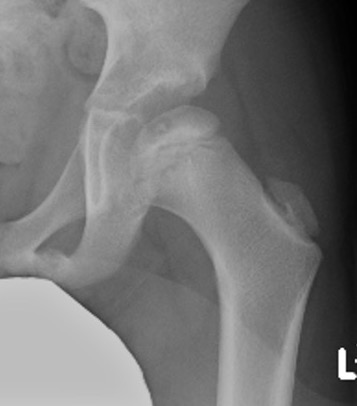

Xray

- may be normal

- small, sclerotic epiphysis

- joint space widening

- increased density of ossific nucleus & cessation of growth

XRay - Fragmentation of Physis

- Better defined shape

- Return of bone density

Xray - May have flattening of the head and neck

Grade stage of Perthes

Lateral Pillar classification